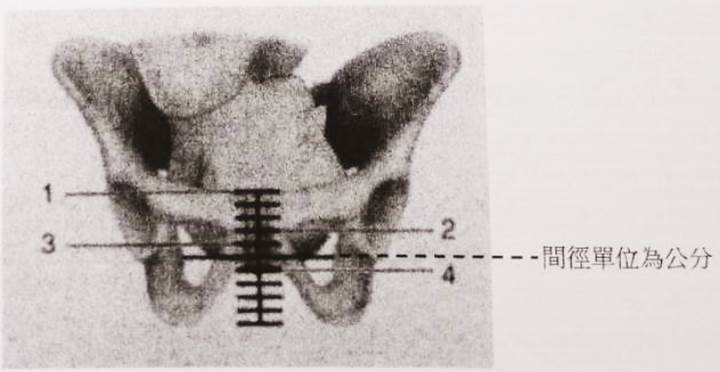

C14 待產婦的護理紀錄記載胎兒先露部位高度是-1。此紀錄結果是指胎兒先露部位為下圖那一個編號的位置?

(A) 1

(B) 2

(C) 3

(D) 4